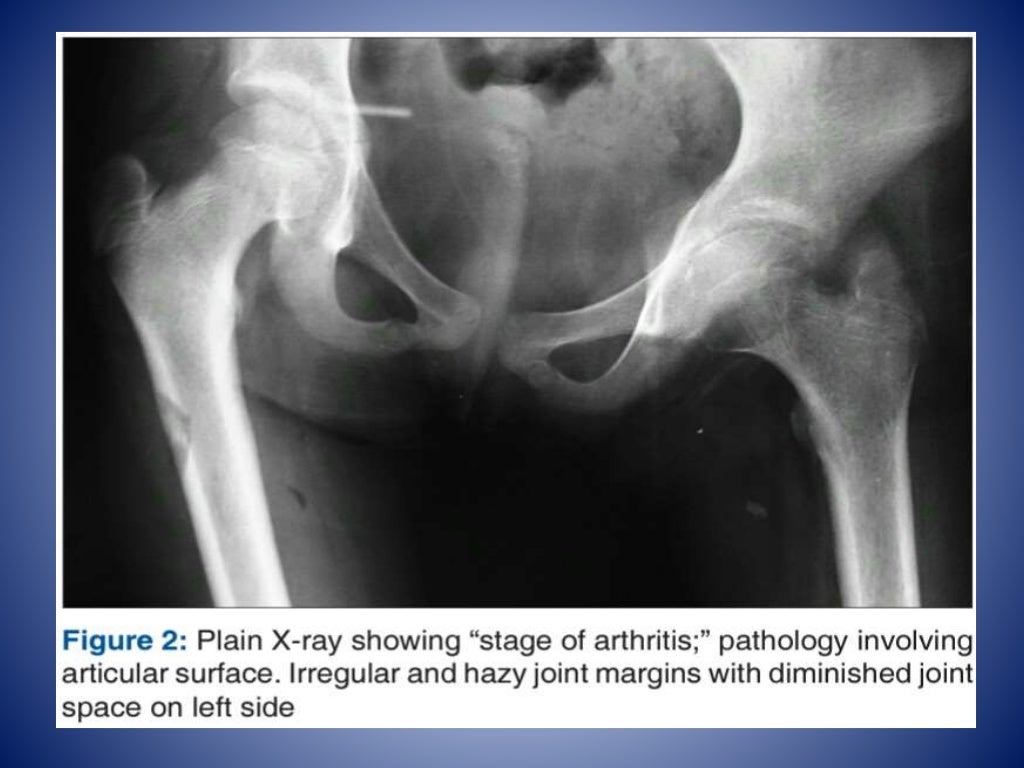

From casereports.bmj.com

A deceptive presentation of Tuberculosis hip as Staphylococcal Hip Joint Tuberculosis Treatment Five out of 18 children with radiologically normal appearing type hip tb were treated with chemotherapy alone and 38. Total hip replacement in tuberculosis of hip is safe and efficient way to save the joint function. Tha is a safe and effective surgical intervention in patients with active and advanced tb arthritis of hip. 4, 5, 6, 7 the. Literature. Hip Joint Tuberculosis Treatment.